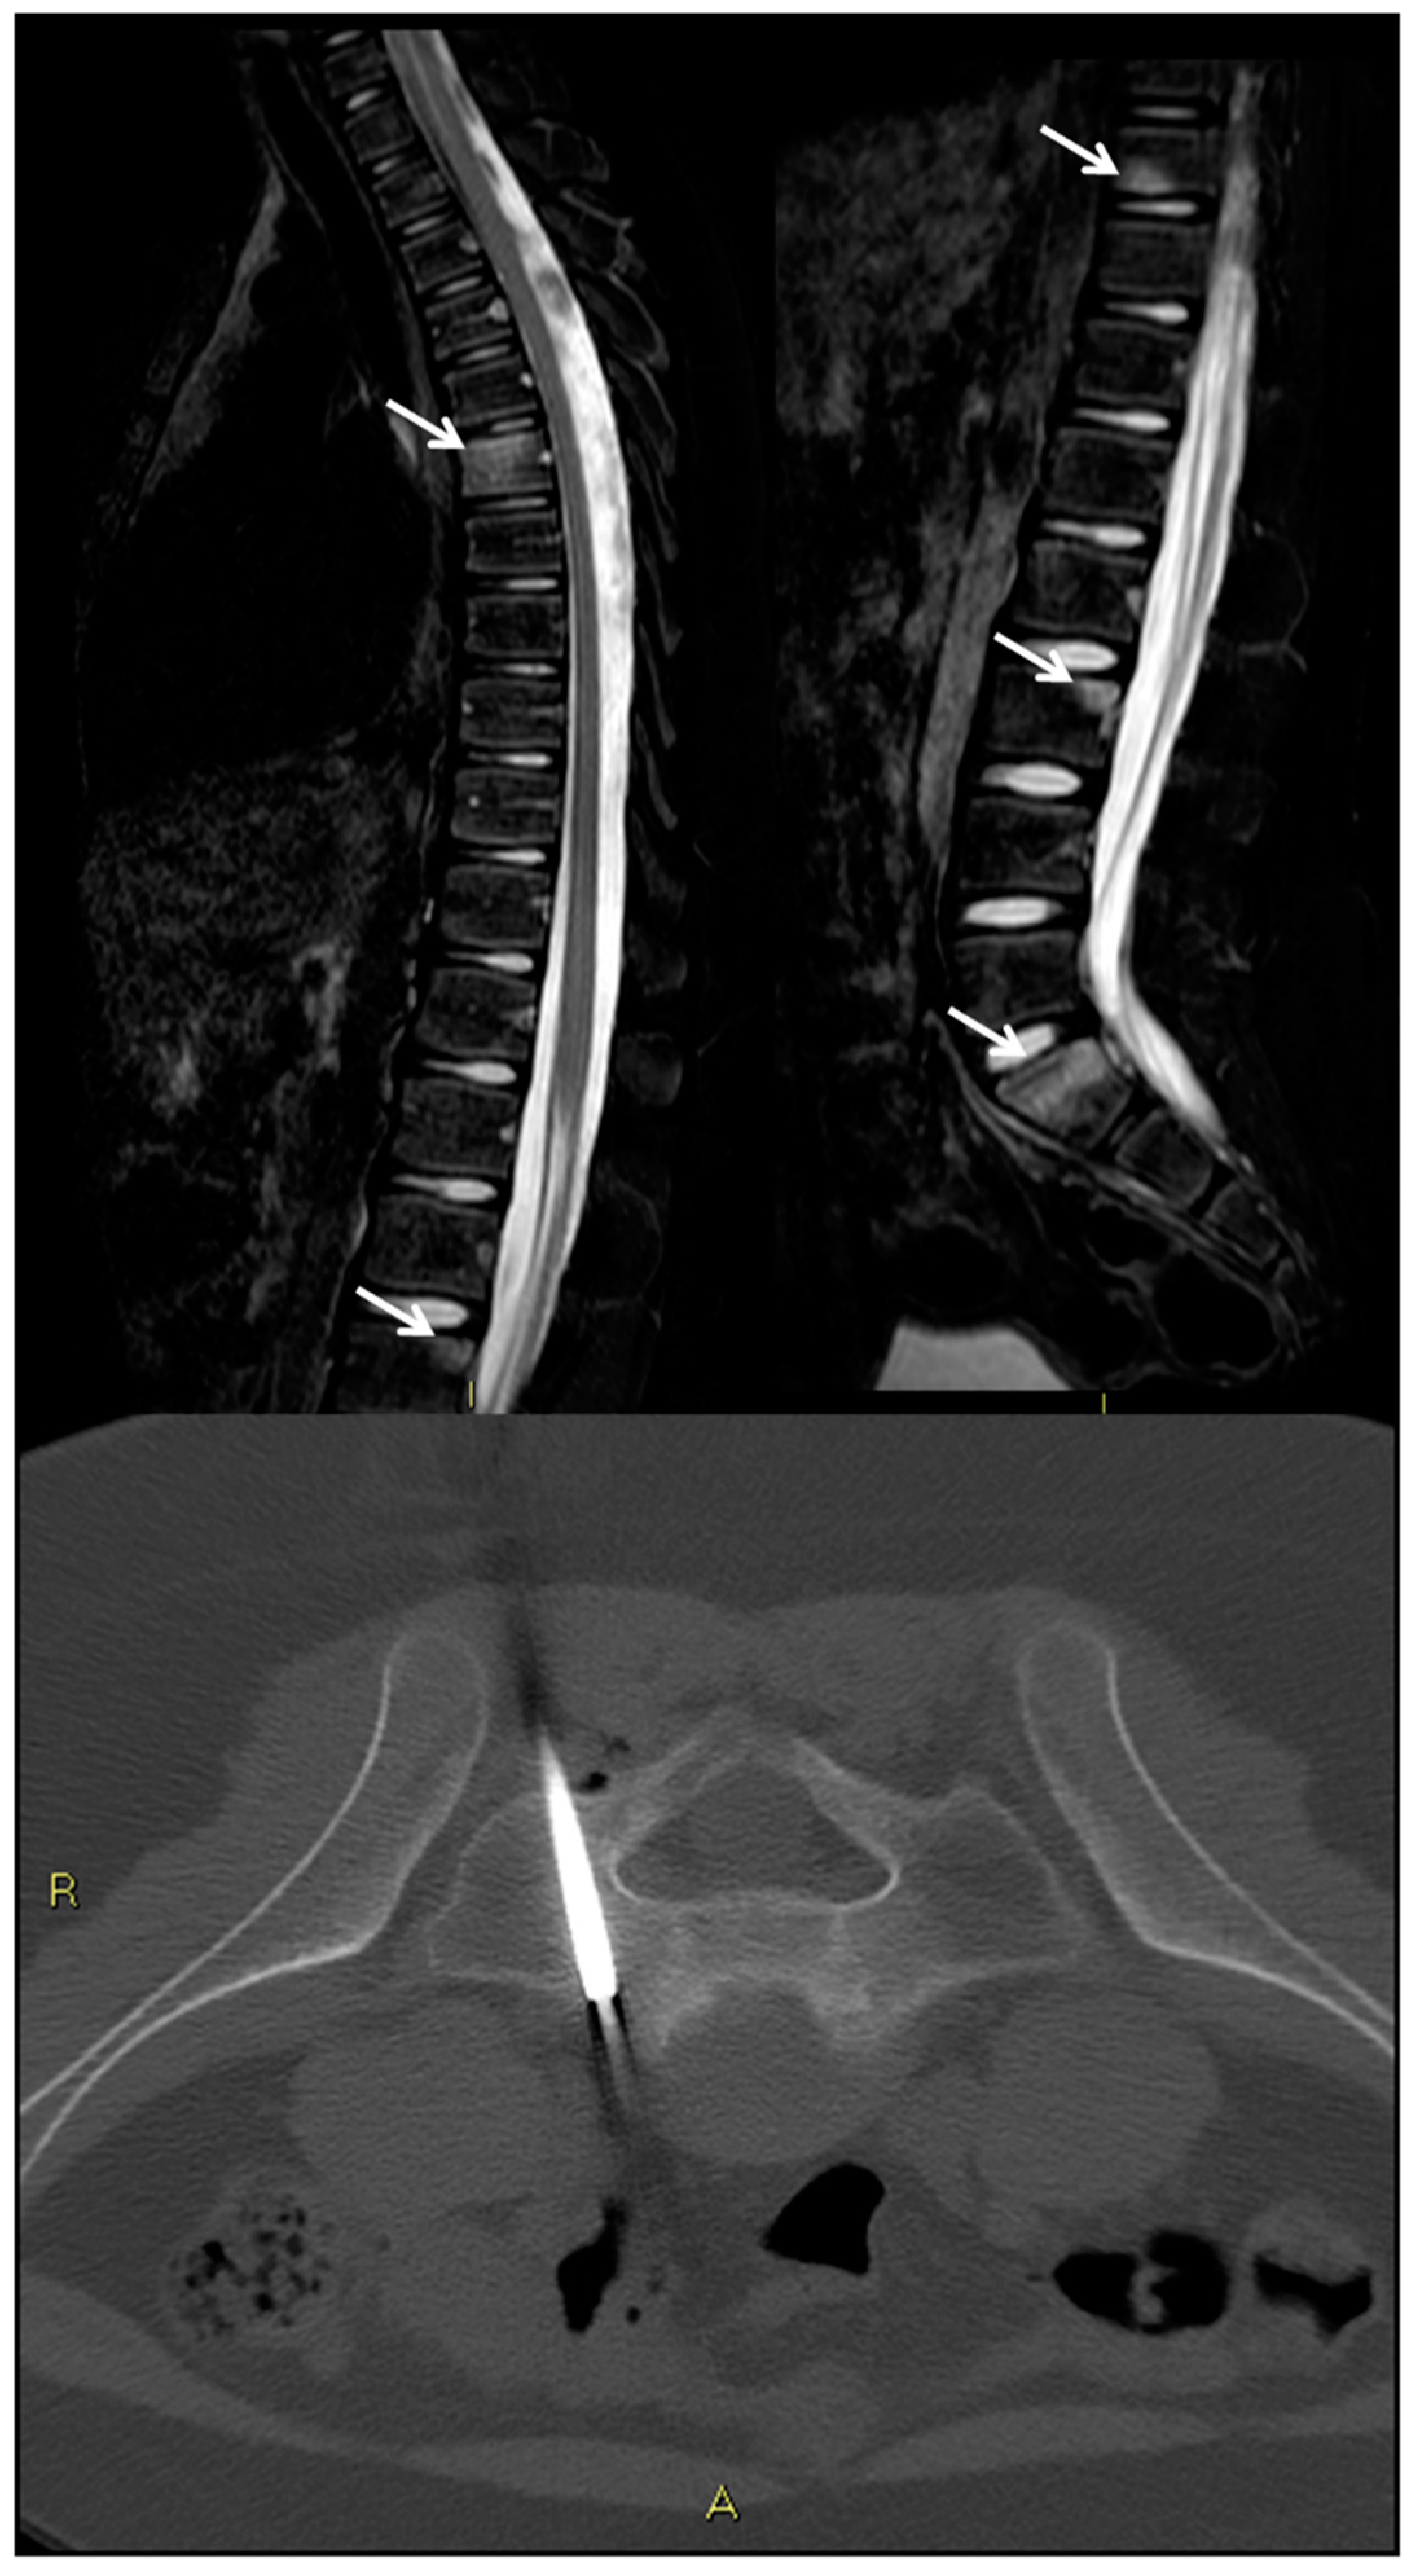

9. Spondylodiscitis

- Michel, S.C.; Pfirrmann, C.W.; Boos, N.; Hodler, J. CT-guided core biopsy of subchondral bone and intervertebral space in suspected spondylodiskitis. AJR Am. J. Roentgenol. 2006, 186, 977–980. [Google Scholar] [CrossRef] [PubMed]